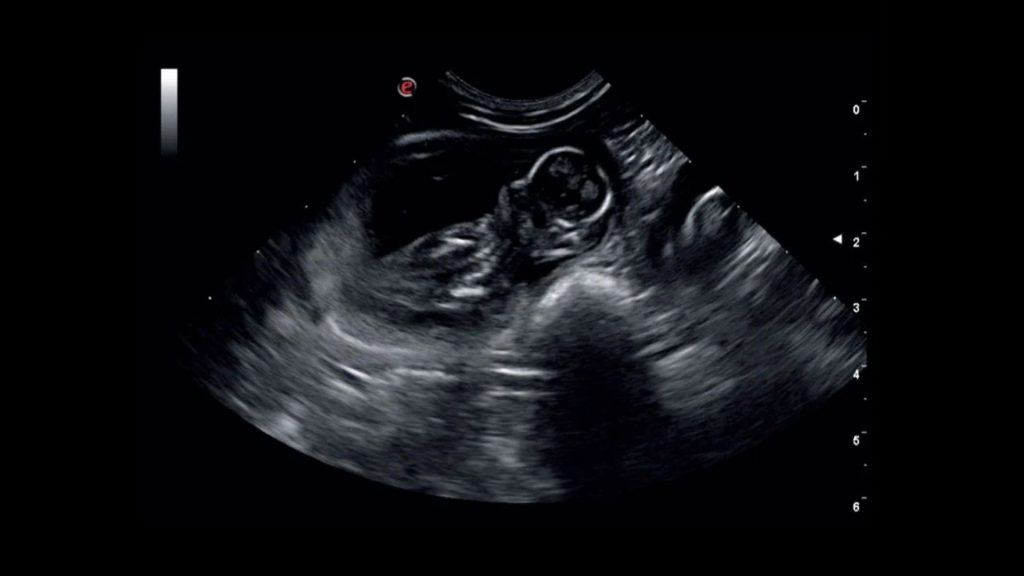

Böbrek ultrasonografisi böbrek fonksiyonuna bağlı olmayan, hasta üzerinde bilinen herhangi bir yan etkisi olmayan, böbrek iç yapısının incelenmesine olanak sağlayan noninvazif bir görüntüleme tekniğidir. Böbreğin ultrasonografik muayenesinde, korteks, medulla ve toplayıcı kanallar görüntülenebilir. Ultrasonografi ile belirlenen böbrek uzunluğu ve hacmi köpeklerde vücut ağırlığıyla doğrusal olarak ilişkilidir. Kedilerde ise ultrasonografi ile belirlenen böbrek uzunluğu 3,0 ila 4,3 cm arasında değişmektedir.

Ultrasonograafik muayene ile tespit edilebilen böbrek hastalıkları; renal kistler, hidronefroz, perinefrik pseudokist, hematom, apse, nekrotik nodüller, tümörler, lenfoma, kronik tubulointerstisyel nefritis, etilen glikol toksisitesi, nefrolitler ve renal agenezidir.

Kan akışına karşı böbrek içi direnç, dubleks Doppler ultrasonografi sırasında değerlendirilebilir ve direnç indeksinin (RI) hesaplanmasıyla değerlendirilebilir.